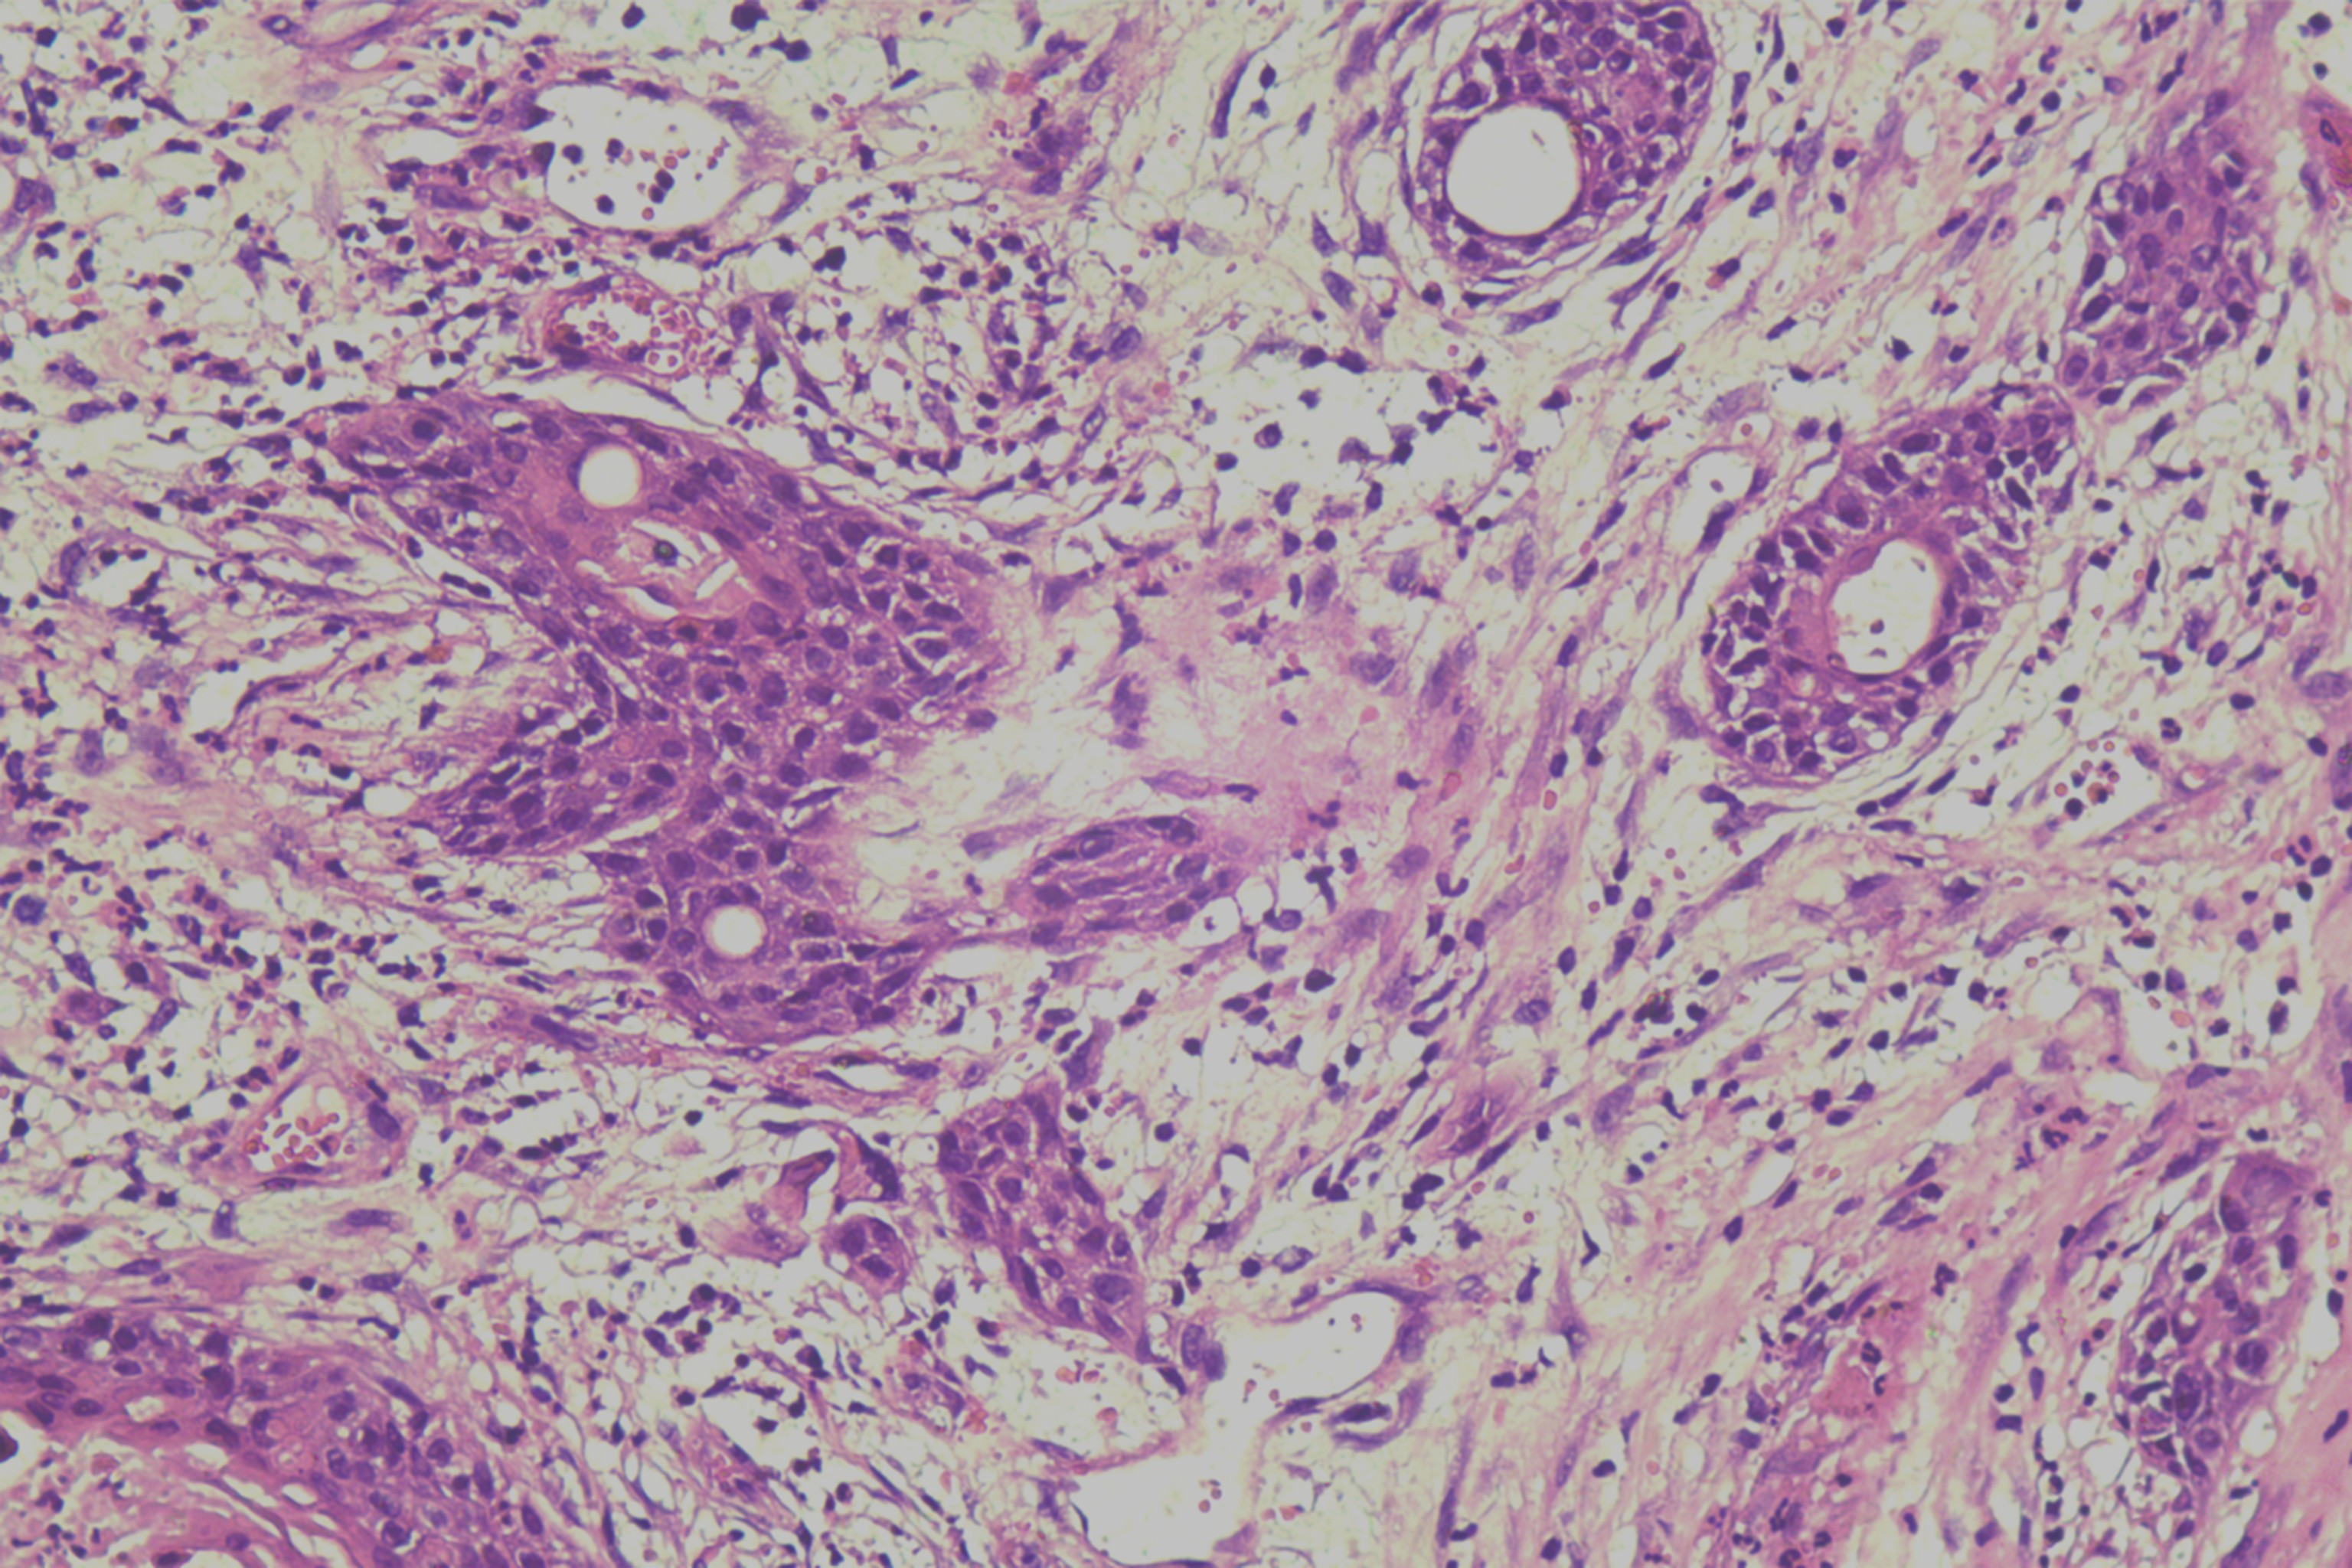

鳞癌?

性别

男

年龄

68岁

头皮肿物20年,包块逐渐增大,反复破溃

头皮肿物(局部活检)

1.5*1*0.3cm灰红碎组织一堆

考虑:基底细胞癌